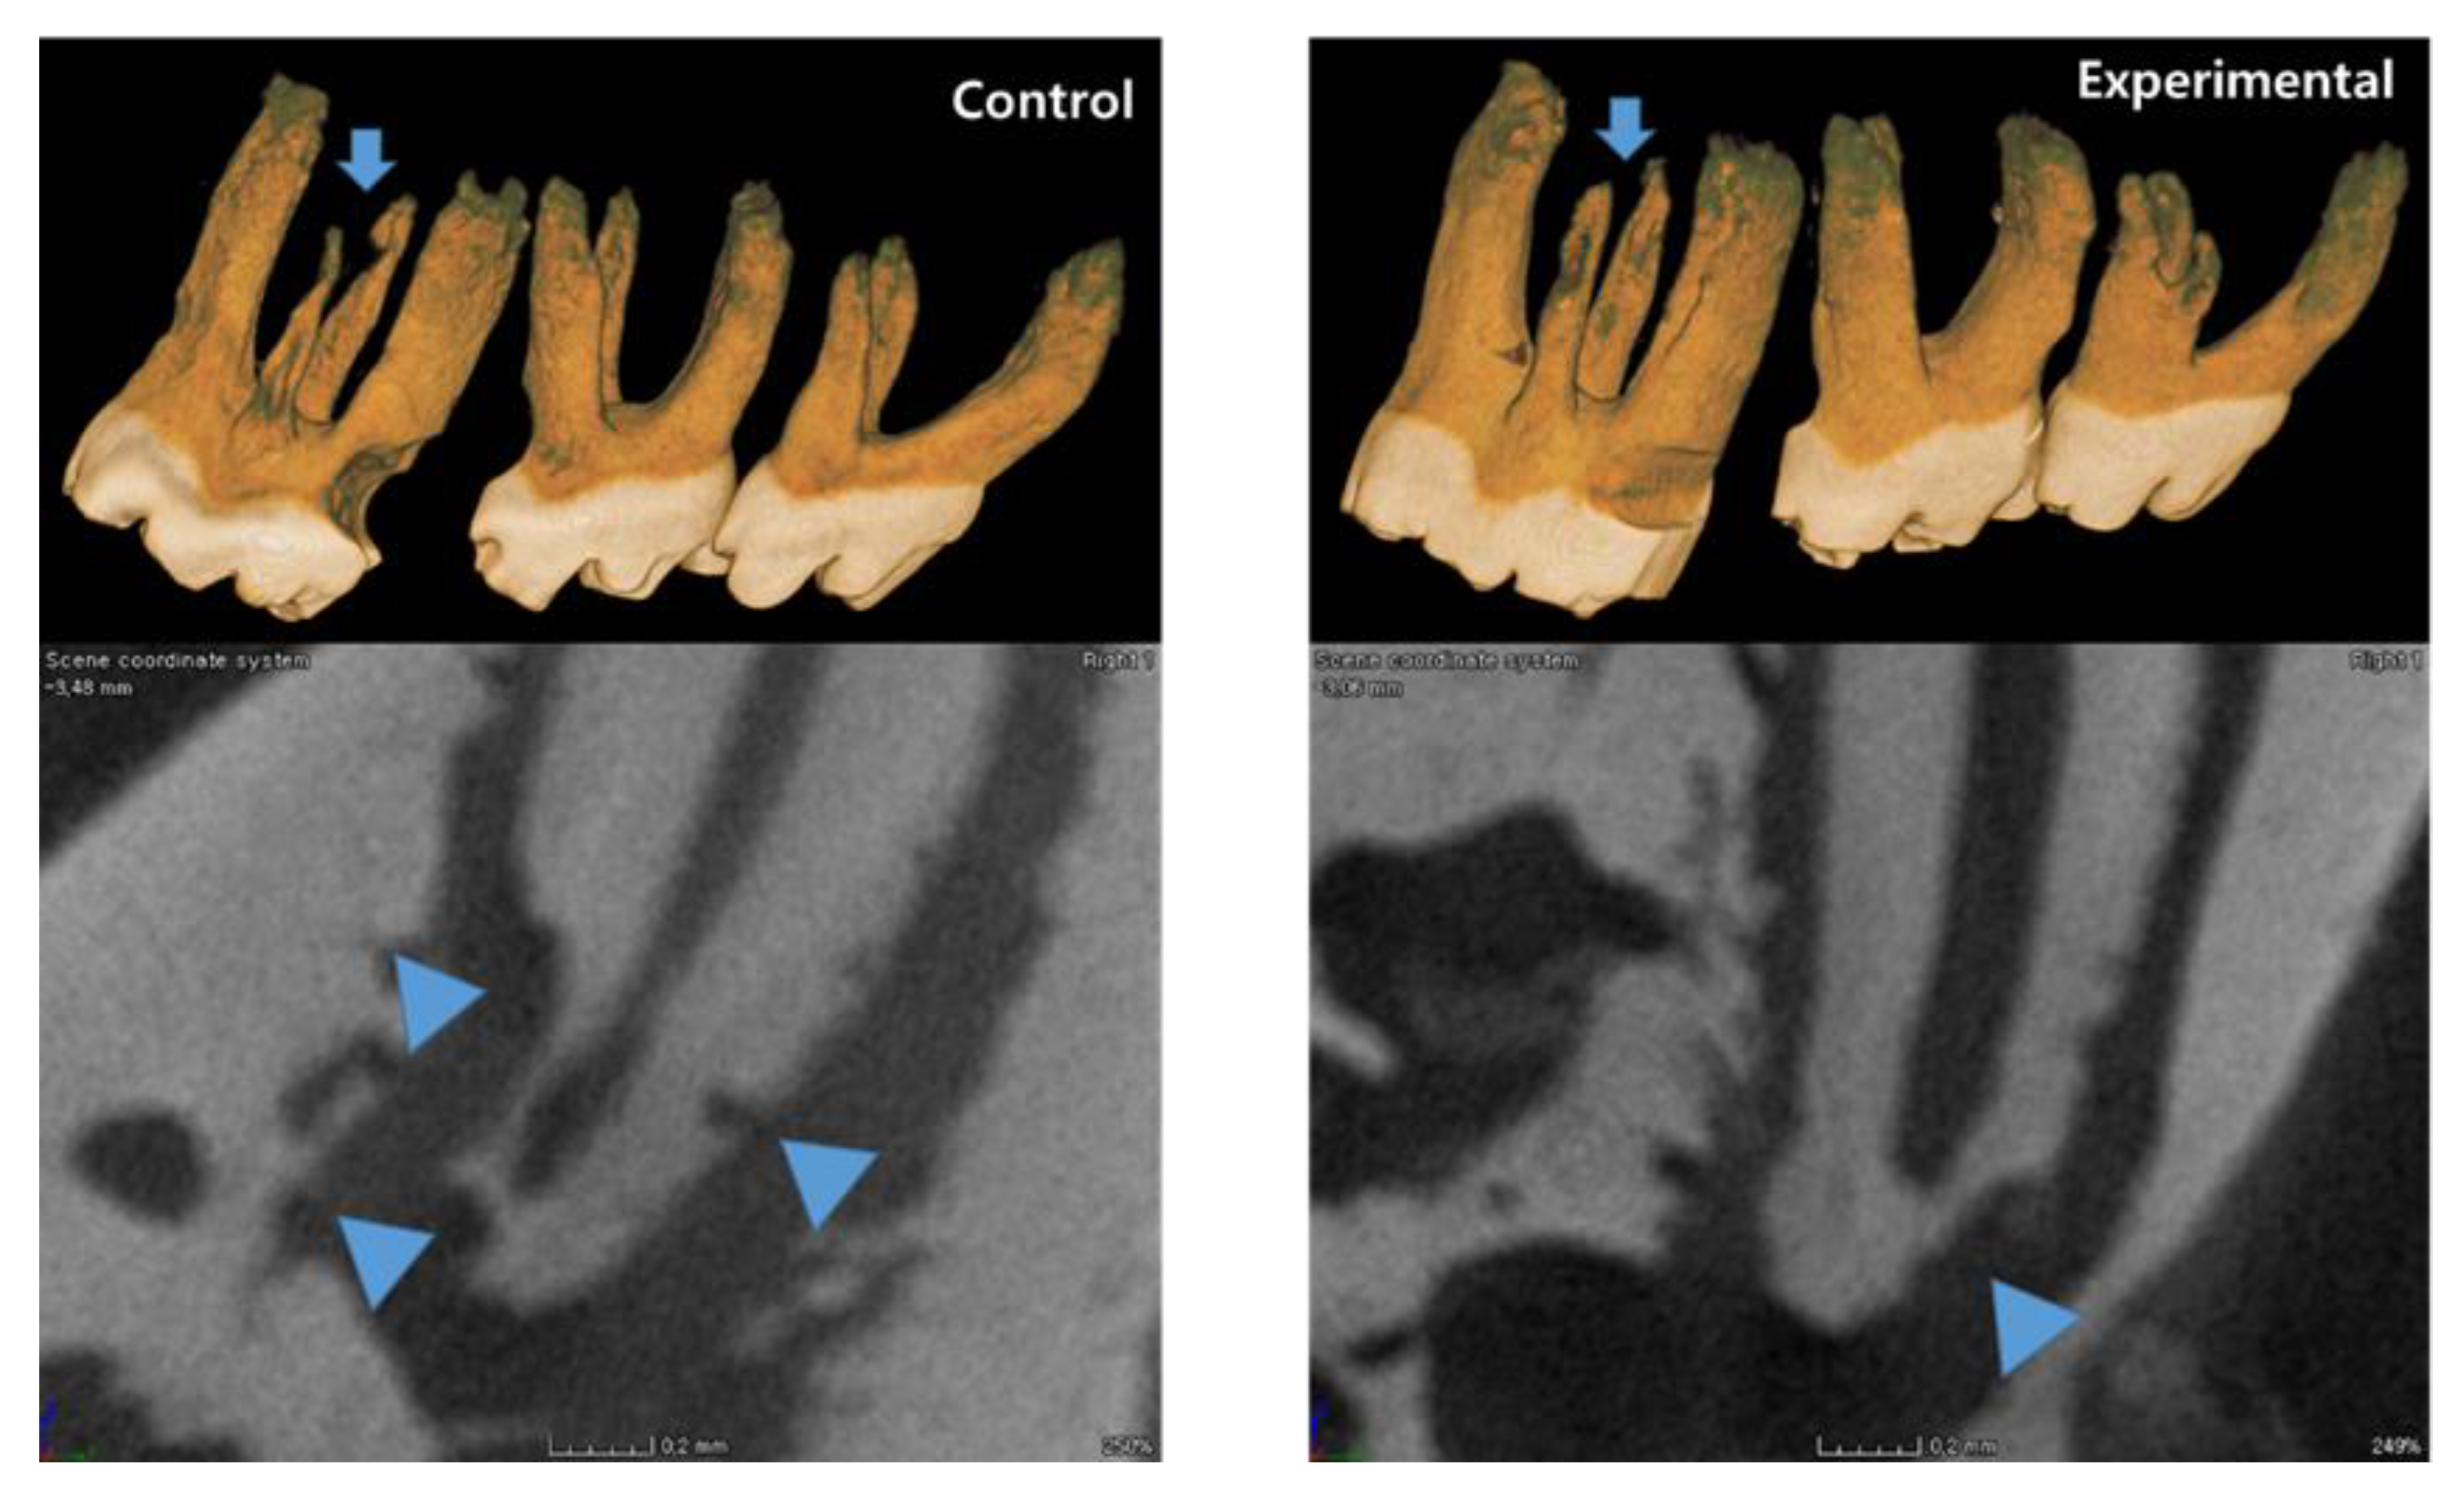

3.1. The Application of 4HR Inhibited Root Resorption during OTM